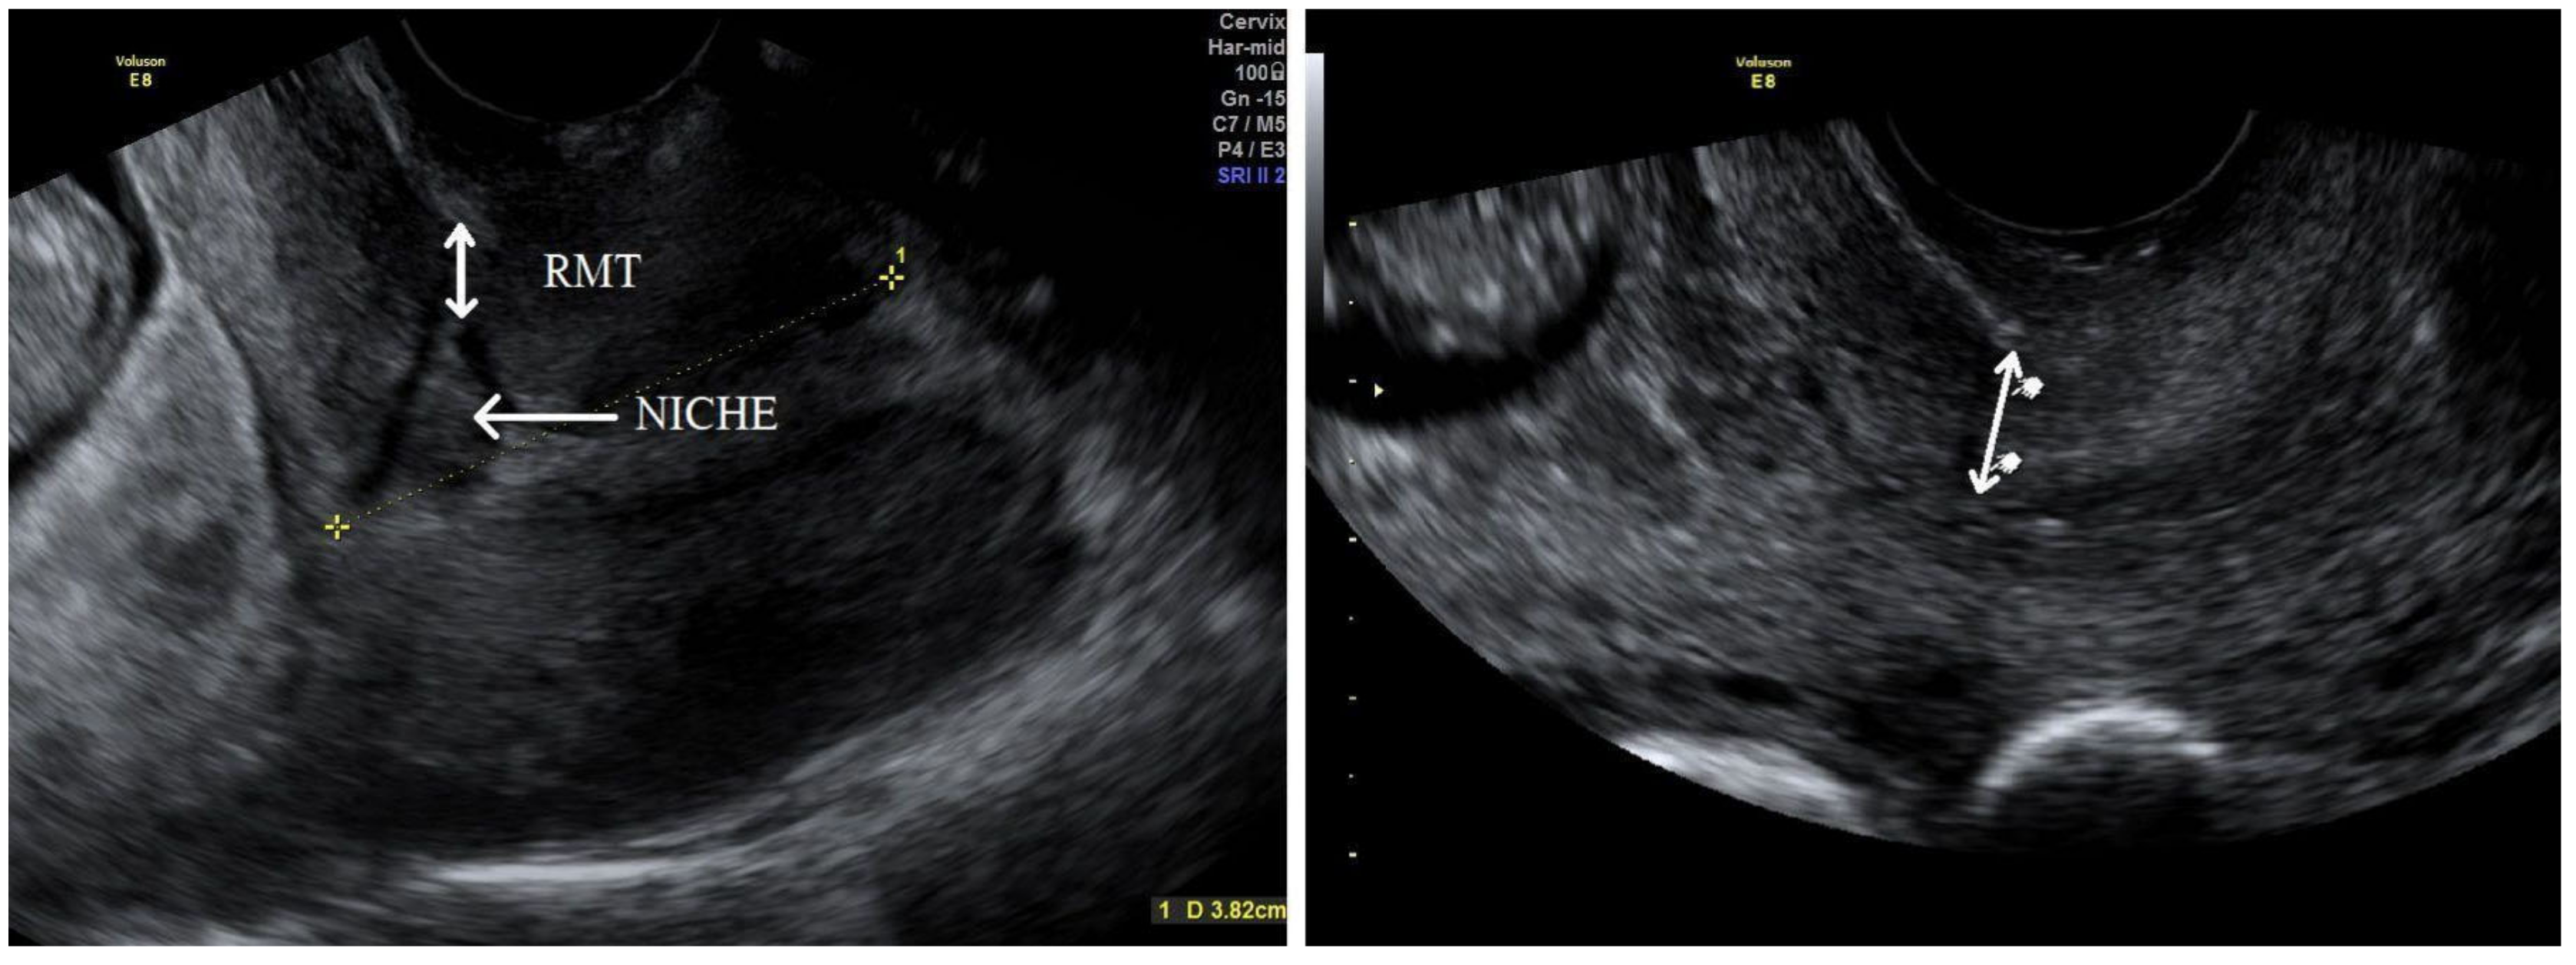

Women over 18 with a singleton pregnancy after at least one previous low-transverse CS and at least twelve months after the last CS were recruited at the 11+0–13+6 week ultrasound screening after the procedures had been explained to them fully. Written informed consent was obtained from all participants and transvaginal ultrasound was performed for a uterine scar examination using a Voluson E8 Expert device (GE Healthcare Ultrasound Korea, Ltd., Seongnam-Si, Korea) with a 4–9 MHz probe. The standardised plane for a CS scar evaluation was performed as a midsagittal view of the uterine isthmus and internal cervical os. CS scar niche was defined as an anechoic area with at least 2 mm depth at the scar site. According to sonographic findings, the study participants were assigned subjectively to the CS scar niche group (niche group) or to the CS scar without niche group (non-niche group). In the CS scar niche group, RMT (distance from the serosal surface of the uterus to the apex of the niche) was measured and presented as CS scar myometrial thickness in the first trimester (Figure 1). The myometrial thickness at the internal cervical os was measured in the non-niche group (Figure 1). Participants needed to have their bladder empty during transvaginal sonography (TVS) in the first trimester. Demographic and obstetric history was obtained during the first scan visit. Second ultrasound examination at 18+0–20+0 weeks and a third at 32+0–35+6 weeks were planned. TVS on a full bladder was used to measure the full LUS and myometrial thickness to delineate the scar area clearly, as was previously described [5] (Figure 2). LUS is a two-layer structure with a hyperechogenic layer, including the bladder wall and a hypoechogenic layer that is considered to represent the myometrium [5] (Figure 2). At least three measurements were taken, with the lowest value being retained. The same investigator was the first researcher (S.E.) and performed all scans as the same ultrasound examination method was applied for CS scar evaluation. All representative images were stored on the local hospital image storage system (MEDDREAM-172.27.1.146). Data were recorded prospectively on an SPSS spreadsheet. Data about pregnancy outcomes and complications were retrieved from an electronic hospital database.

Figure 1. First-trimester midsagittal ultrasound images showing the evaluation of residual myometrial thickness (RMT) (on the left) in the CS scar niche participant group and evaluation of myometrial thickness at internal cervical os (on the right) in the non-niche participant group.